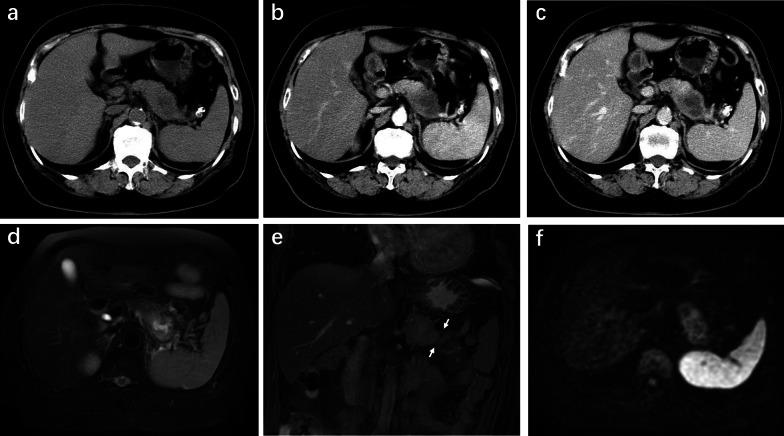

Patients with pancreatic MiNEN more frequently presented with large size and heterogeneous and cystic components compared with PDAC (p < 0.031) and ill-defined irregular margins, progressive enhancement, and adjacent organ involvement compared with NET (p < 0.036). However, vascular invasion was less commonly seen in MiNEN than PDAC (p = 0.010). Moderate enhancement was observed more frequently in MiNEN than in PDAC or NET (p < 0.001). Multivariate logistic analyses demonstrated that moderate enhancement and ill-defined irregular margin were the most valuable features for the prediction of pancreatic MiNEN (p ≤ 0.044). The combination of the two features resulted in a specificity of 93.8%, sensitivity of 83.3%, and accuracy of 91.7%.

We have mainly described the radiological findings of pancreatic MiNEN with ill-defined irregular margin and moderate enhancement compared with PDAC and NET. The combination of imaging features could improve diagnostic efficiency and help in the selection of the correct treatment method.